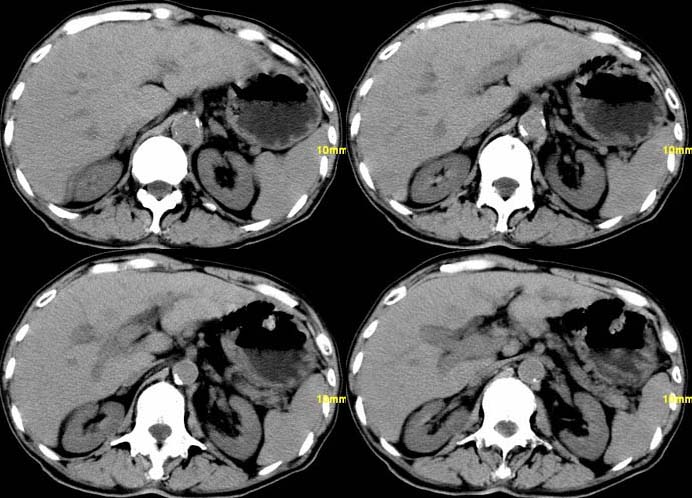

以下是引用余辉在2007-12-6 22:23:00的发言:[br]胆囊内多枚结石影,胆管全程扩张,右肝内病灶强化符合脓肿表现现(左肝病灶图像未传完),考虑急性梗阻性化脓性胆囊胆管炎合并肝多发脓肿(建议补传左肝病灶图像)